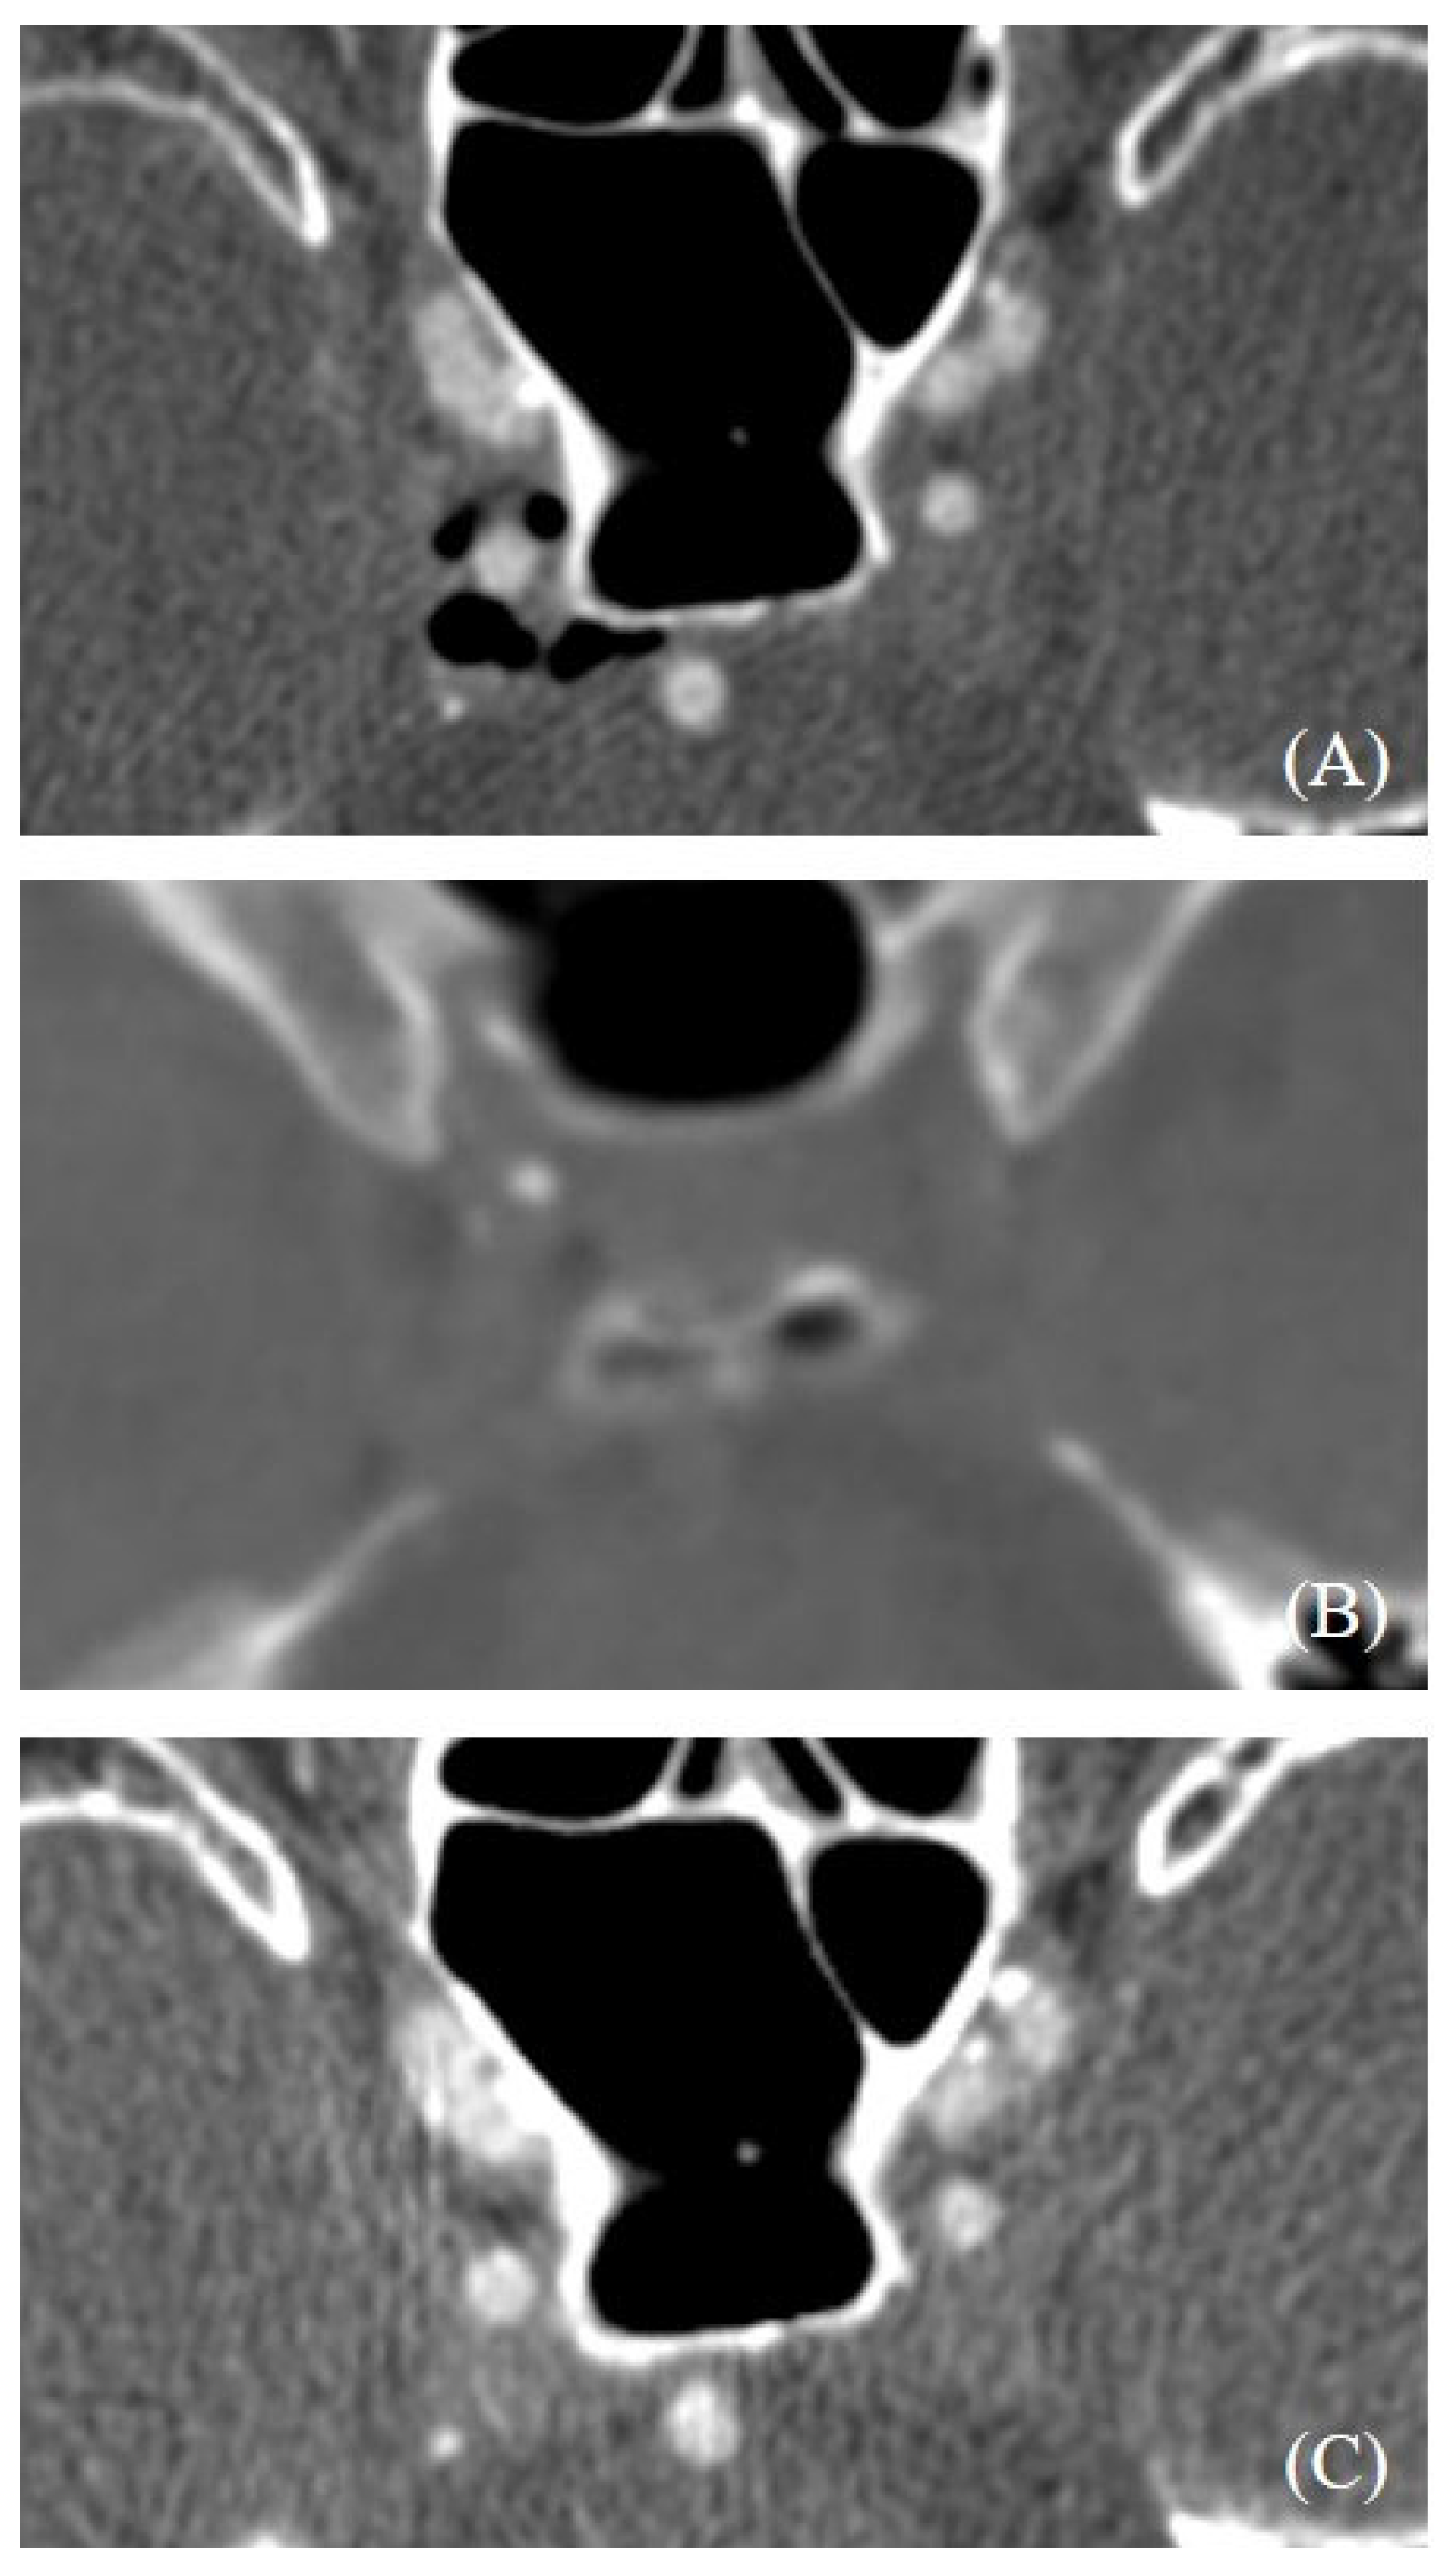

2. Materials and Methods

2.1. Patient Selection

2.2. Imaging Protocol

2.3. Image Interpretation